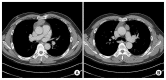

The actual incidence of multiple thymoma is unknown and rarely reported because it remains controversial whether the cases represent a disease of multicentric origin or a disease resulting from intrathymic metastasis. In this case, a patient underwent total thymectomy for multiple thymoma with myasthenia gravis via bilateral video-assisted thoracic surgery. A well-encapsulated multinodular cystic mass, measuring 57 mm×50 mm×22 mm in the right lobe of the thymus, and a well-encapsulated mass, measuring 32 mm×15 mm×14 mm in the left lobe, were found. Both tumors were type B2 thymoma. Few cases of multiple thymoma with myasthenia gravis have ever been reported in the literature. We report a case of synchronous multiple thymoma associated with myasthenia gravis.